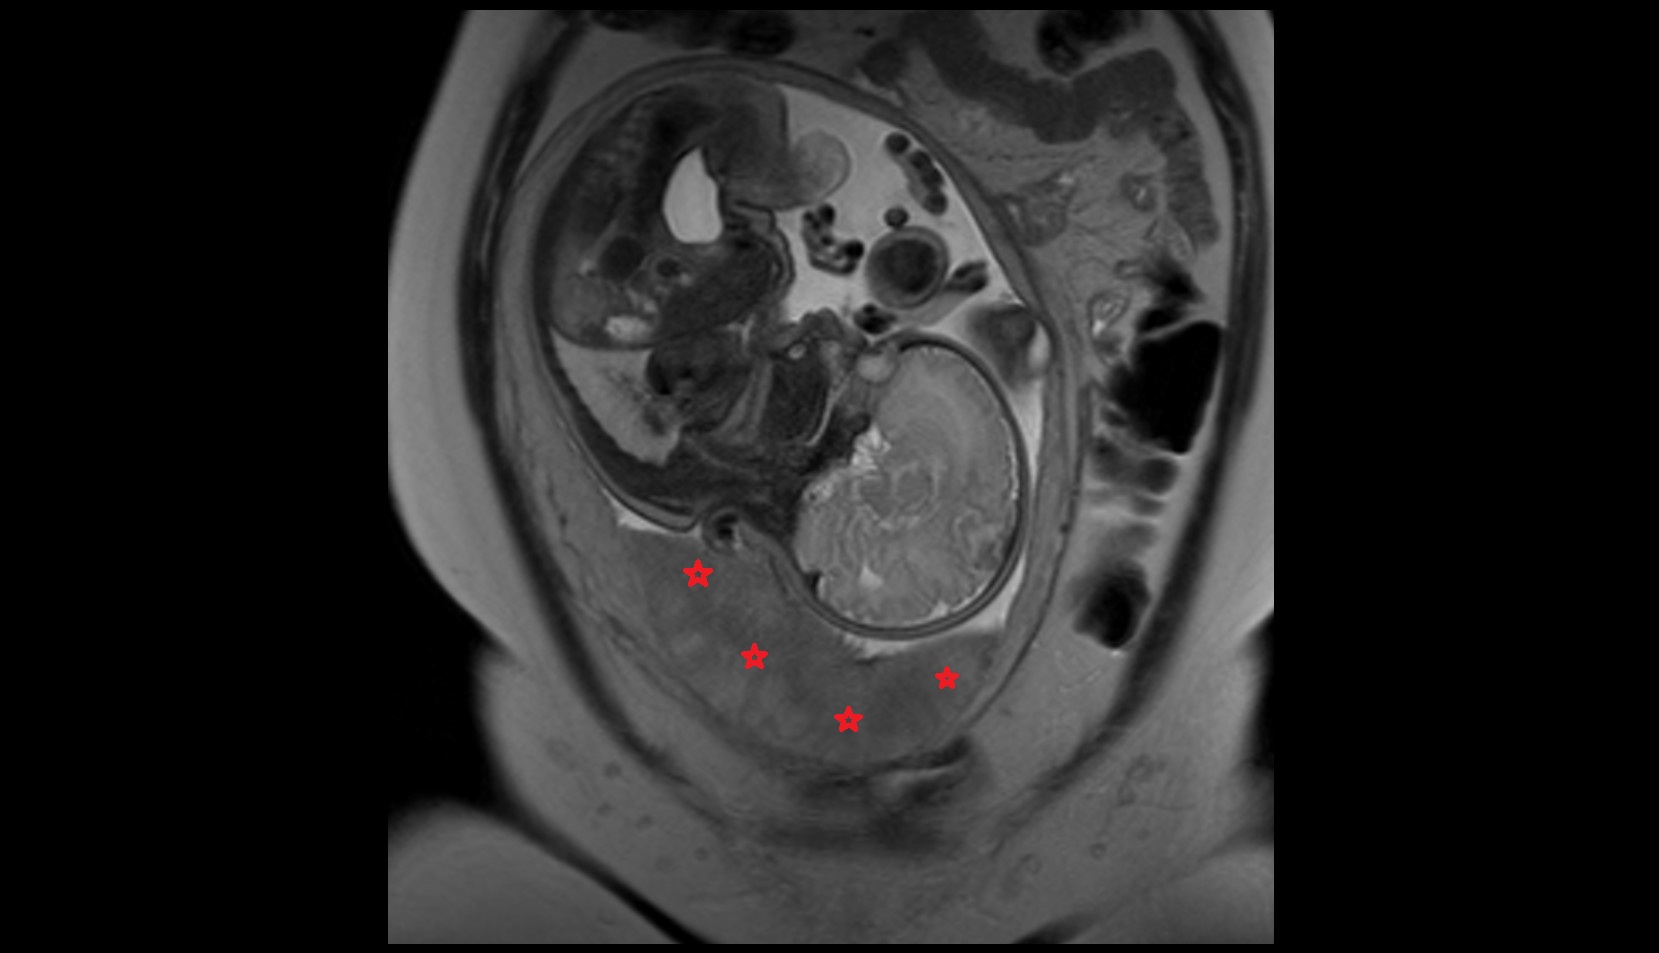

- Placenta

- Uterus (pregnancy)

- Amniotic fluid

- Umbilical cord

- Fetal brain

- Fetal cerebellum

- Fetal occipital lobe

- Fetal temporal lobe

- Fetal parietal lobe

- Fetal frontal lobe

- Fetal lateral ventricle

- Fetal Liver

- Fetal small bowel

- Fetal kidneys